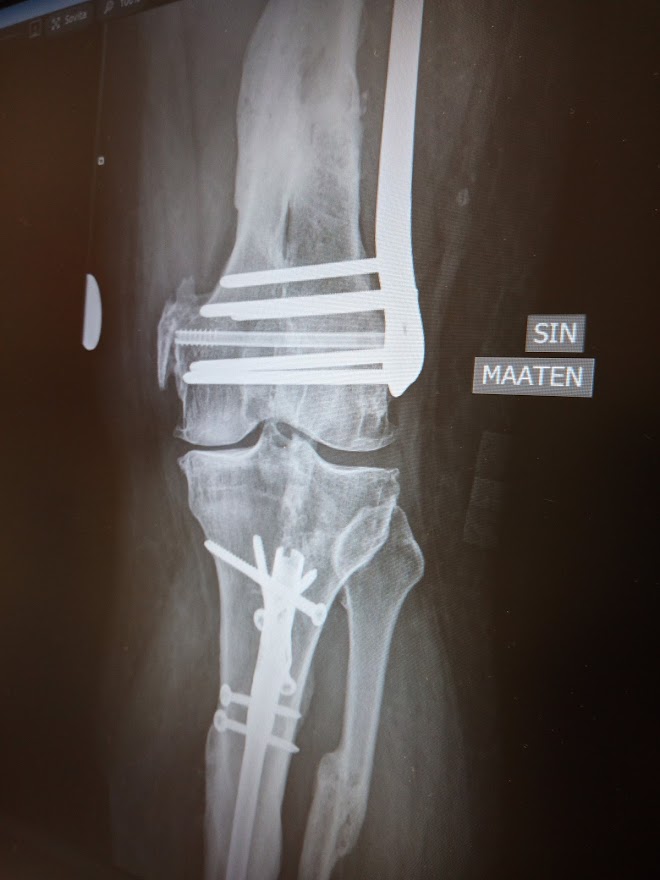

Aloitan jalkani telomisesta.... :(

Poikki on ja eiku leikkaukseen...

Rautaa ja ruuveja on kuin pienessä rautakaupassa... :p